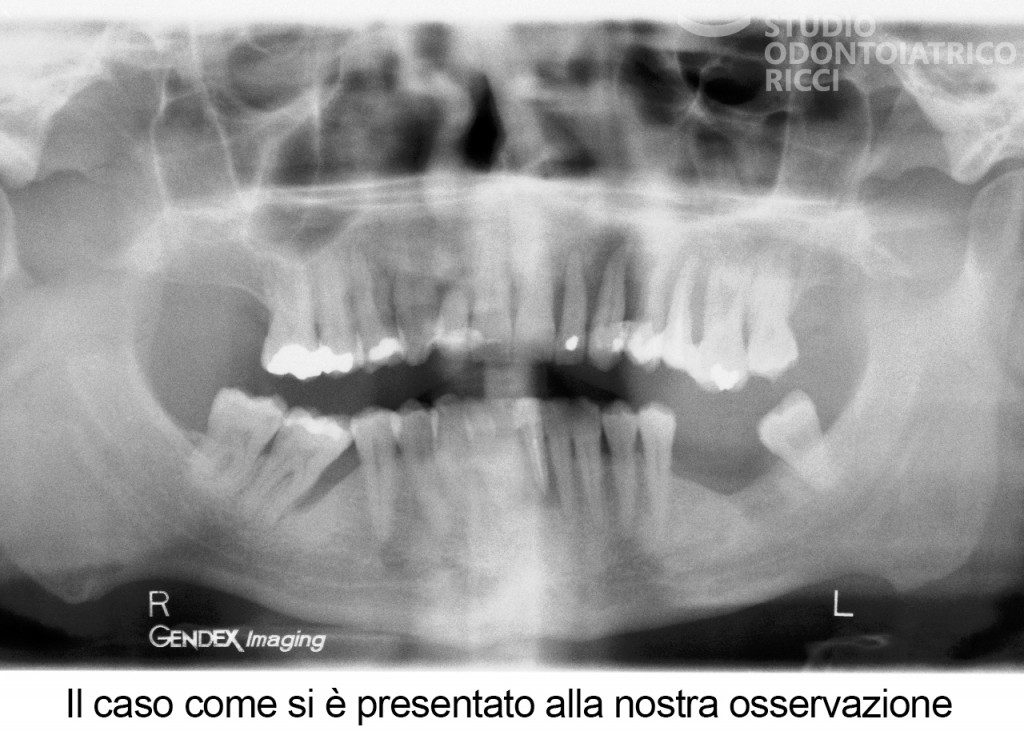

La maggior parte dei pazienti può sottoporsi a un trattamento implantare. È però fondamentale eseguire uno studio preliminare, con esami radiografici (es. TAC) per valutare:

quantità e qualità dell’osso